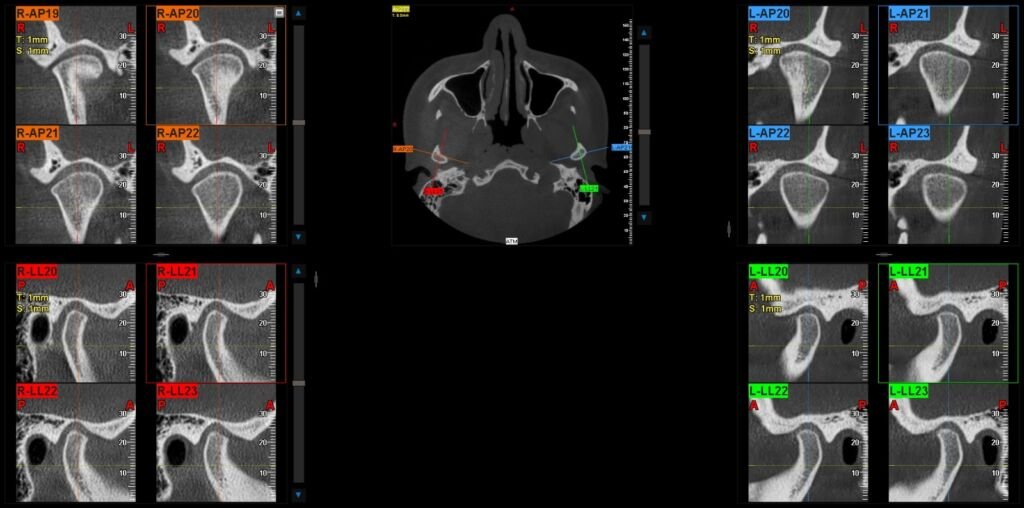

Imágenes 2D-3D Radiografías, Tomografías DENTAL, ATM, SPN, OIDO

Nuestra tecnología Cone Beam 3D permite visualizar estructuras óseas y dentales con alta definición, favoreciendo diagnósticos exactos y resultados clínicos confiables.

¿Qué es el Tac dental maxilar y cómo puede ayudarte?

El Tac dental maxilar, también conocido como tomografía computarizada de haz cónico (CBCT, por sus siglas en inglés), es una …